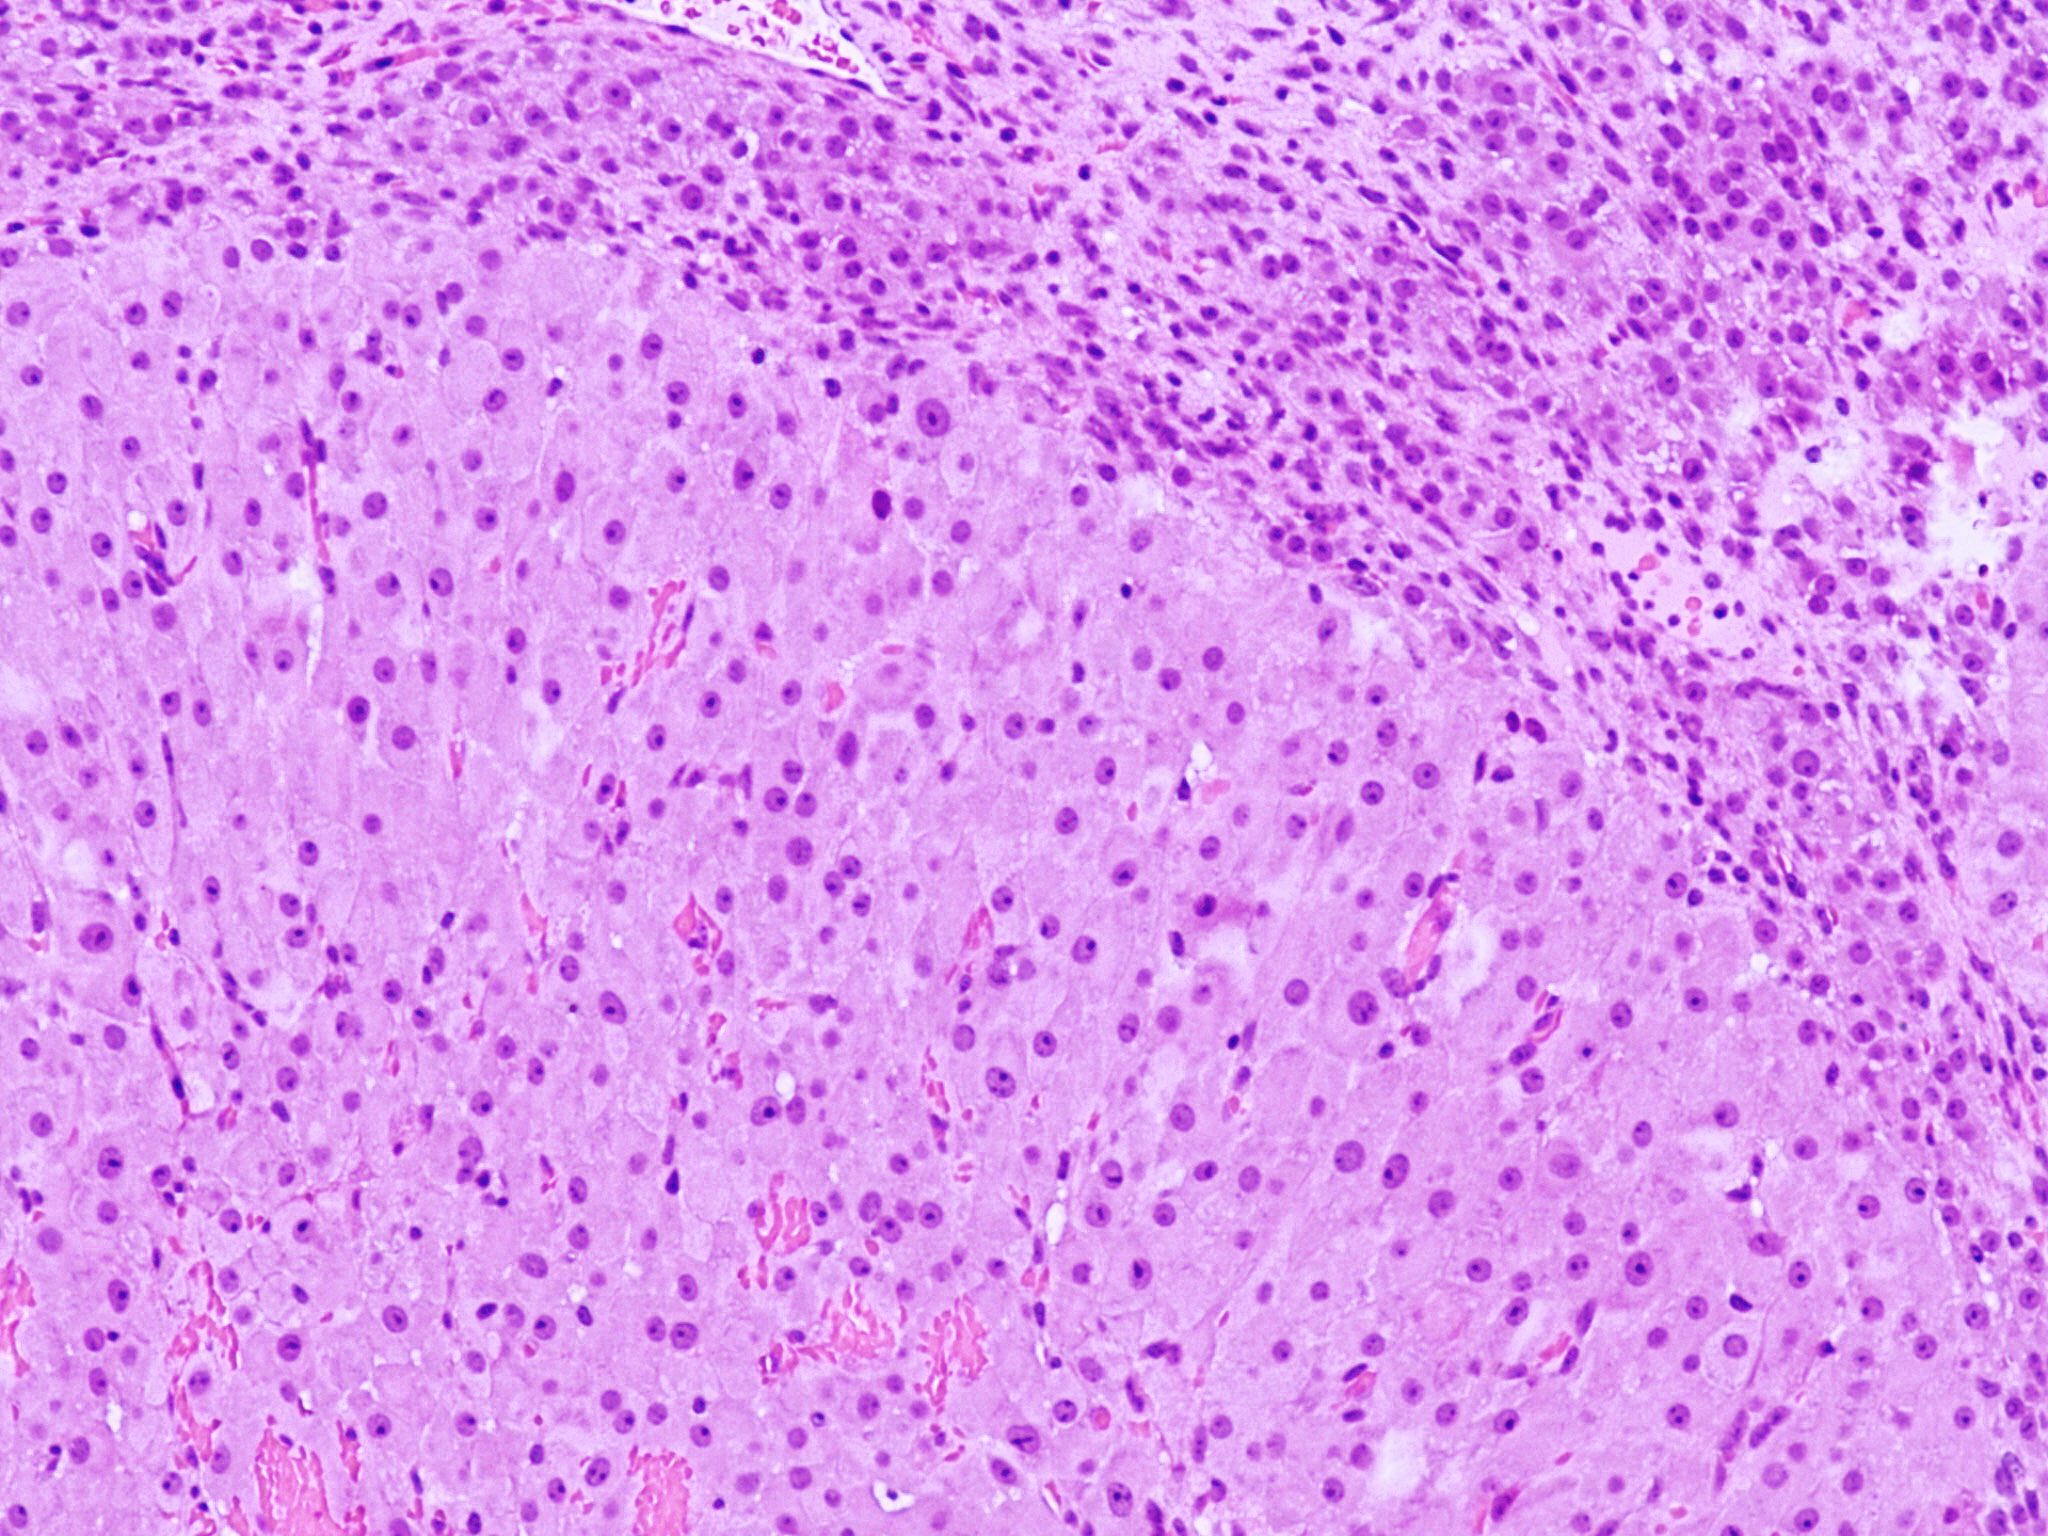

Microscopic (histologic) description

- Cyst lining is convoluted, composed of an inner layer of luteinized granulosa cells and outer layer of theca cells

- Granulosa cells are polygonal in shape, with abundant eosinophilic cytoplasm and central round nuclei

- Mitotic figures may be seen in the granulosa cells

- Outer theca cells are smaller in size

- Prominent inner layer of fibrous tissue

- Reference: Kurman: Blaustein's Pathology of the Female Genital Tract, 7th Edition, 2019

Microscopic (histologic) images